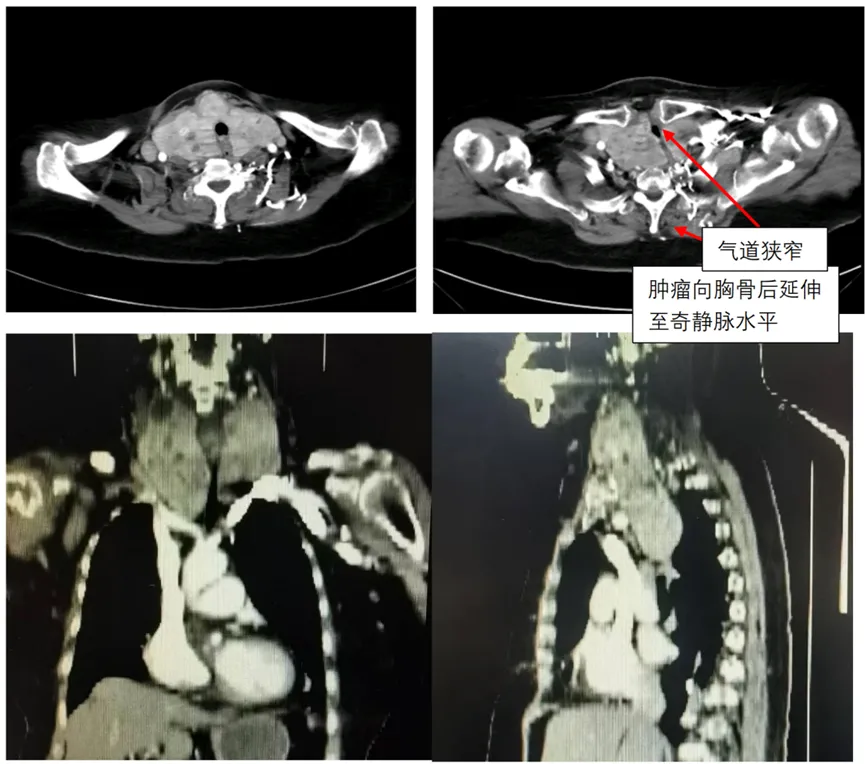

丝路驿站的生命邂逅仔细检查后,两位专家发现了更为复杂的情况。影像检查显示,老人颈部的巨大甲状腺肿瘤已延伸至纵膈达奇静脉水平,造成气道严重狭窄。更棘手的是,患者还伴有中重度肺功能障碍、急性肺部感染,以及高血压和冠心病等多种基础疾病。任何一个并发症都可能让手术风险成倍增加。